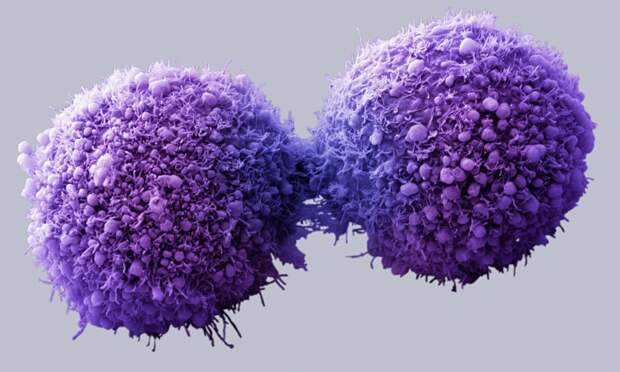

Каждую минуту ваше тело производит раковые клетки. Однако их появление не приводит к раку, потому что ваша иммунная система разрушает их